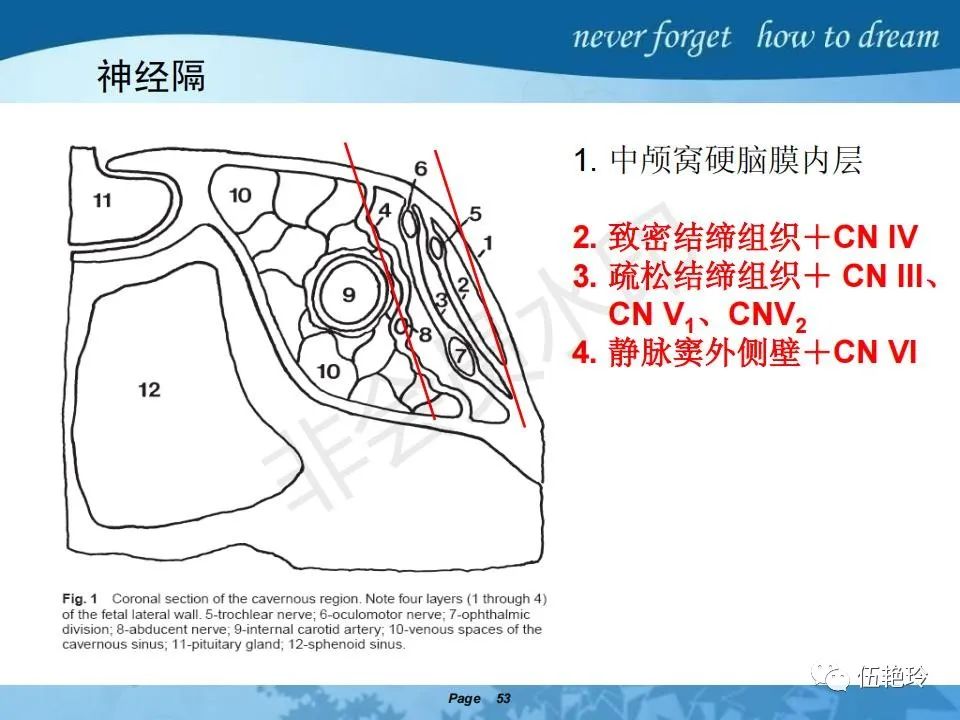

海绵窦区的解剖结构与鼻咽癌侵犯